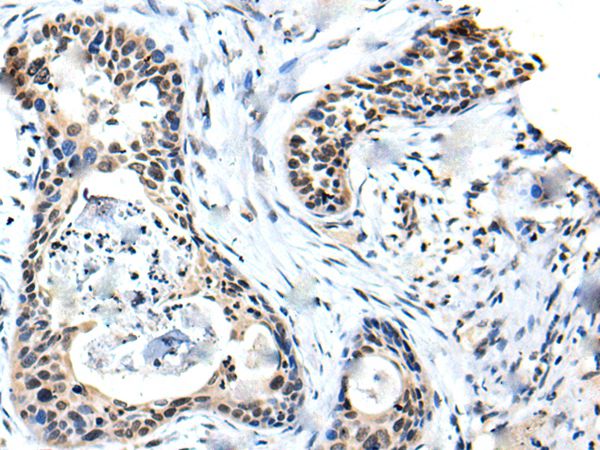

分类: 科研抗体货号: P43469别名: 45170应用: WB,IHC反应种属: Human